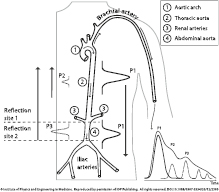

The ejection of blood from the left ventricle creates a pressure wave called the arterial pulse pressure wave. As the main pressure wave (P1—illustrated in figure 1) travels down the systemic vascular network, it reaches several sites causing reflection due to significant changes in arterial resistance and compliance. The first one is the juncture between thoracic and abdominal aorta, which causes the first wave reflection (P2—illustrated in figure 1) and commonly known as the second or late systolic wave. At the second reflection site, the juncture between the abdominal aorta and common iliac arteries, the main wave is reflected once again, and appears as a second wave reflection (P3—illustrated in figure 1) (Baruch et al 2011). A small dip, called the dicrotic notch, is commonly observed between the first and second wave reflections (P2 and P3, respectively). There are additional minor reflections and re-reflections in the systemic vascular structure with lower amplitudes of the reflection waves. These pulse reflections are also observed in a similar, but smoother, fashion in the photoplethysmogram morphology (O'Rourke 1995, Goswami et al 2010).

Figure 1. Morphology and origin of the PPG pulse. Left: a sketch of the arterial system from the aorta/arm to the iliac arteries. Right: a PPG pulse decomposed in the correspondent forward pulse (P1) and pulses reflected at the first (P2) and second (P3) reflection sites. Reproduced from Coucerio et al (2014) with permission of IOP Publishing.